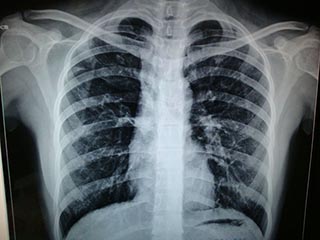

x光有辐射是从所周知的事情,说x光对人有一定影响,说x光完全无害那就是在扯蛋。有些准备要生育的家庭就担心x光的辐射会影响到怀孕。那么拍x光对精子有影响吗?x光会不会使精子......